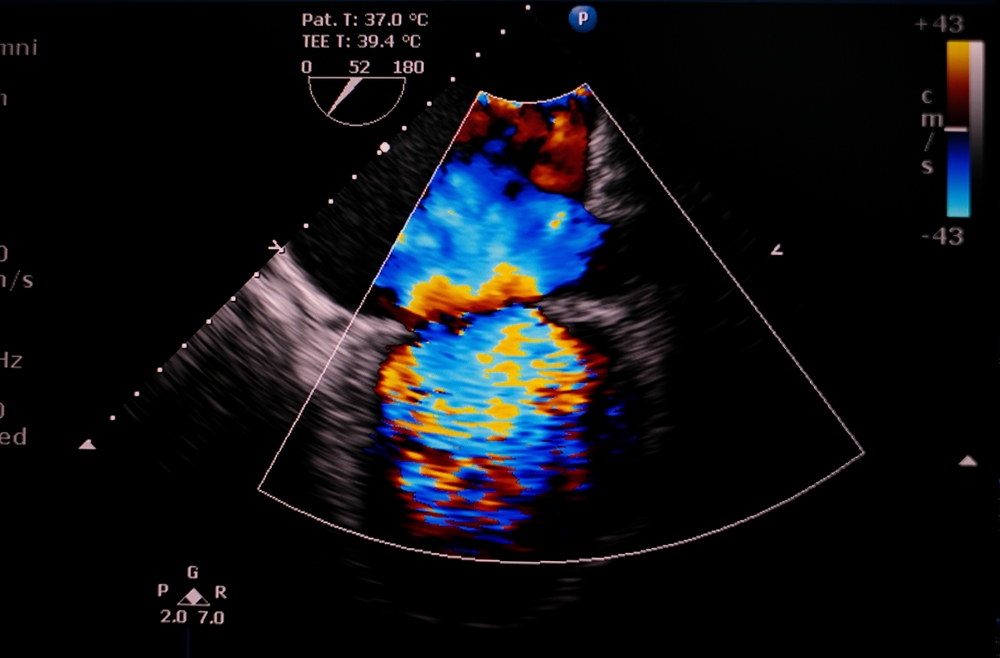

Η εμφύτευση βηματοδότη ή απινιδωτή είναι ζωτικής σημασίας σε ασθενείς με αρρυθμίες ή κίνδυνο για αιφνίδιο καρδιακό επεισόδιο. Όμως, σε ένα 5-10% των ασθενών αυτών τα καλώδια των συσκευών, που περνούν μέσα από την τριγλώχινα βαλβίδα, θα προκαλέσουν σοβαρή ανεπάρκεια της βαλβίδας. Οι μηχανισμοί με τους οποίους προκαλείται η ανεπάρκεια της τριγλώχινας βαλβίδας είναι πολλαπλοί. Τα καλώδια μπορεί να πιέζουν μια γλωχίνα της βαλβίδας, να έχουν τρυπήσει μια γλωχίνα, ή και να ενοχλούν την λειτουργία του υποβαλβιδικού μηχανισμού που στηρίζει την βαλβίδα.

Στην περίπτωση που κριθεί ότι ο ασθενής χρειάζεται επέμβαση προτιμάται η επιδιόρθωση της βαλβίδας σε σχέση με την αντικατάσταση. Η επιδιόρθωση σε πολλές περιπτώσεις μπορεί να πραγματοποιηθεί ελάχιστα επεμβατικά με θωρακοσκοπική μέθοδο και με πάλλουσα καρδιά. Ο καρδιοχειρουργός θα αναλύσει την αιτία της δυσλειτουργίας και θα μετακινήσει ή θα αφαιρέσει το καλώδιο που προκαλεί την ανεπάρκεια. Στην συνέχεια θα εφαρμόσει τεχνική για την επιδιόρθωση της γλωχίνας, αν χρειαστεί, και συνήθως θα τοποθετηθεί ένας δακτύλιος στην περίμετρο της βαλβίδας. Σε λίγες περιπτώσεις με εκτεταμένο τραυματισμό της βαλβίδας μπορεί να χρειαστεί να γίνει αντικατάσταση της βαλβίδας. Σε ασθενείς με πολλαπλές ιατρικές παθήσεις που είναι αυξημένου χειρουργικού κινδύνου μπορεί να εφαρμοστεί η διαδερμική επιδιόρθωση ή αντικατάσταση της τριγλώχινας βαλβίδας. Πρέπει να τονιστεί ότι η χειρουργική επιδιόρθωση παραμένει ή πρώτη επιλογή για τους περισσότερους ασθενείς λόγω των ανώτερων μακροπρόθεσμων αποτελεσμάτων.